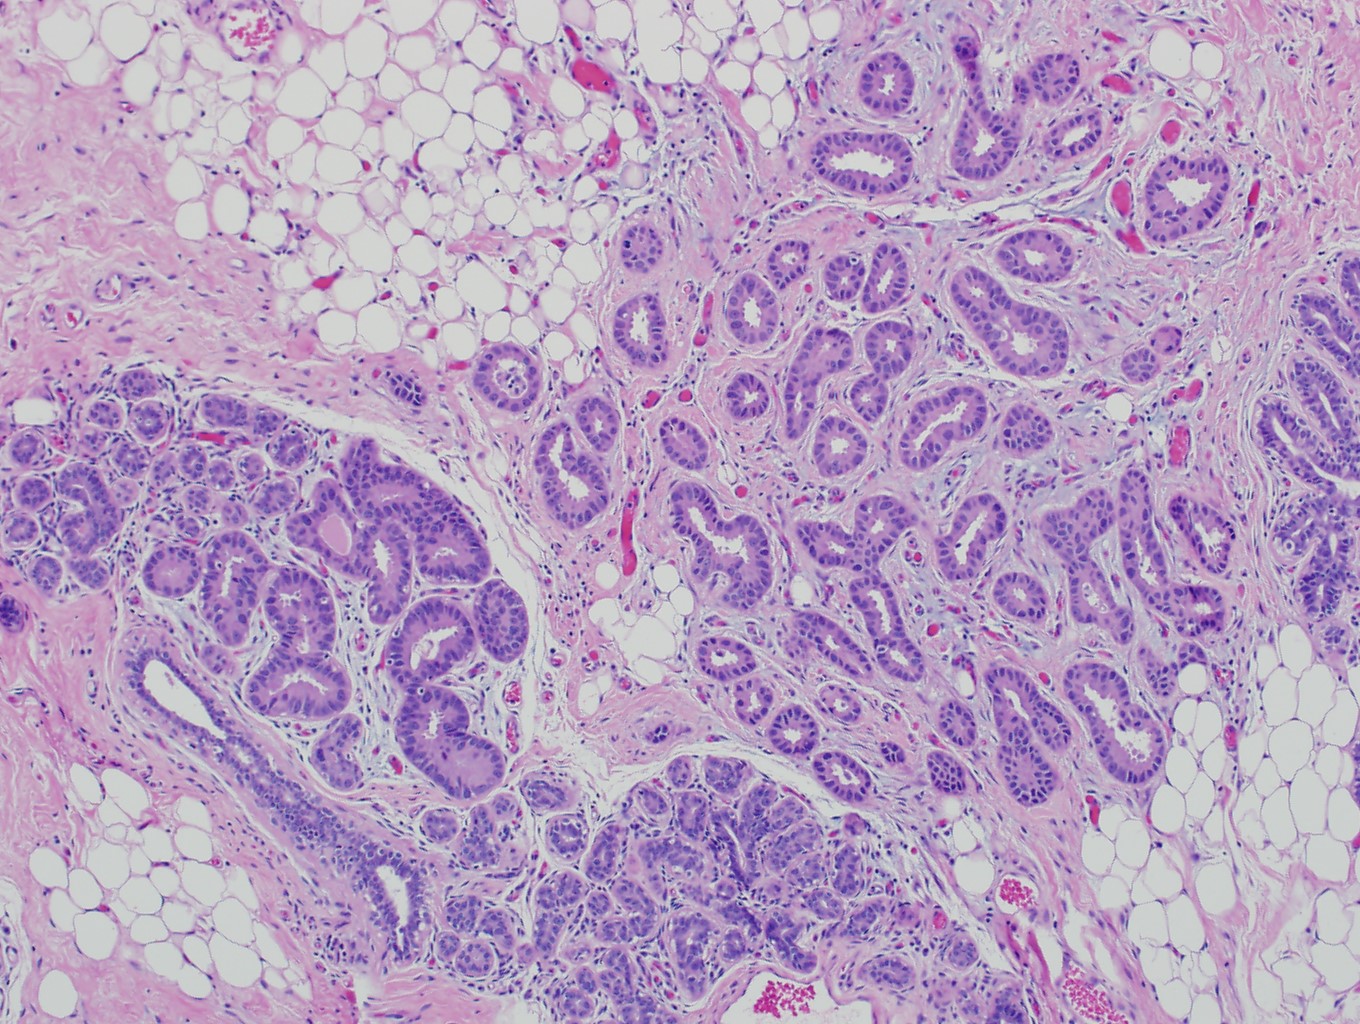

Microscopic (histologic) description

- Histological features of IBC NST vary considerably from case to case and even within the same case

- Margins vary from highly infiltrative, permeating the surrounding tissue, to continuous pushing margins

- Architecture varies from sheets, nests, clusters, cords or individual cells (but lacks the cytomorphological characteristics of invasive lobular carcinoma)

- Tubular formations are prominent in well differentiated tumors but absent in poorly differentiated tumors

- Variable cytological features:

- Cytoplasm may be abundant and eosinophilic but it can show other features in some tumors, including as clear, foamy or granular

- Nuclei may be regular and uniform or highly pleomorphic with prominent or multiple nucleoli

- Mitotic figures are variable from virtually absent to extensive

- 2 distinct growth patterns exist:

- Large and solid nests or syncytial infiltrative growth pattern with little associated stroma and an expansive growth that compresses the surrounding stroma (e.g., most basal-like breast cancers)

- Tumors characterized by small cancer nests accompanied by marked fibrosis (desmoplastic / scirrhous); this type diffusely infiltrates the surrounding tissue as an irregular shaped spiculated mass

- Often ductal carcinoma in situ (DCIS) (up to 80%)

- In some cases, DCIS is extensive

- Associated DCIS is usually of same nuclear grade as the invasive carcinoma

- Perineural invasion (28%)

- No myoepithelial cell lining (as seen in DCIS or benign lesions)

Microscopic (histologic) images

Contributed by Julie M. Jorns, M.D., Kristen E. Muller, D.O., Gary Tozbikian, M.D. and Emad Rakha, M.D.